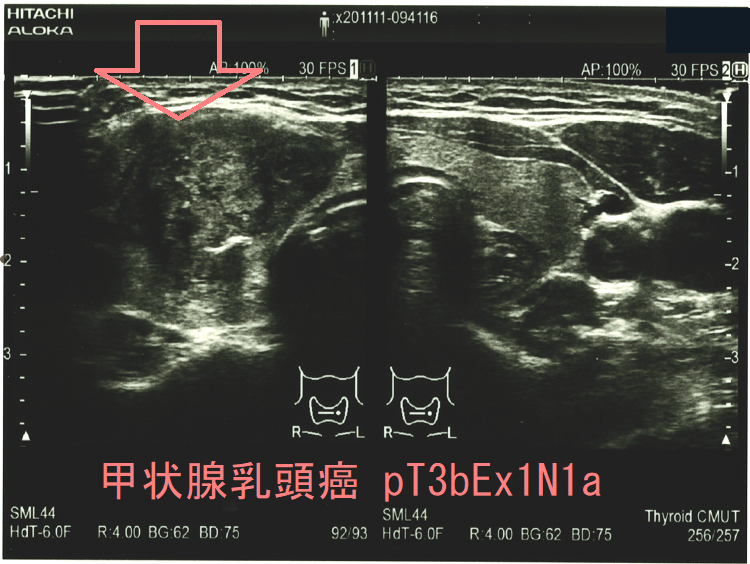

よって、それらのリスクを冒してまで予防的外側区域リンパ節郭清を行うのは、どの様な症例でしょうか?隈病院外科によると、

①甲状腺乳頭癌の大きさが

3cmを超えると術後10年のリンパ節再発率13%

3cm未満は2%

②Ex2(浸潤が被膜を越えEx1以外の組織、臓器におよぶ)の術後10年リンパ節再発率14%

Ex0(浸潤が被膜を越えない)あるいはEx1(浸潤が被膜を越えるが、胸骨甲状筋か脂肪組織に留まる)は5%

※Ex1a(周囲の脂肪組織に及ぶ)、Ex1b(前頸筋群、副甲状腺に及ぶ)

なので、3cm以上、またはEx2が予防的外側区域リンパ節郭清の適応になります。(日本内分泌・甲状腺外科学会雑誌 Vol. 29 (2012) No. 2 p. 123-125)